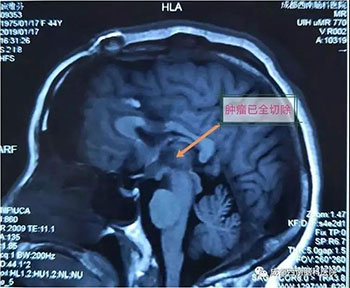

中脑海绵状血管瘤手术

术前

术后

颅眶沟通性肿瘤切除手术

术后(肿瘤全切)